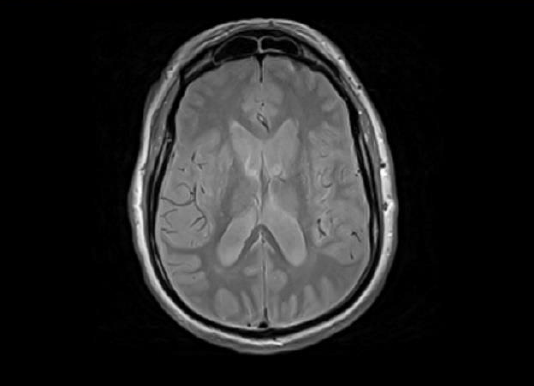

In an MRI image, in addition to sections of the brain, there are also non-brain tissues, such as fat, skull or neck, which can cause problems with the analysis [38]. Brain extraction, also known as ”skull-stripping”, describes the process of removing the skull and non-brain tissues from brain MRI scans. it is a method for segmenting the brain from non-brain into structural and functional data. [53]. It is also a necessary processing step in most studies for compliance with privacy regulations. For these reasons, several brain extraction algorithms (BEAs) are available in neuroradiological research [35].

First, a mask is generated to identify brain tissues that include the grey matter, white matter, and cerebrospinal fluid of the cerebral cortex and subcortical structures, such as the brain stem and cerebellum. The scalp, hard matter, fat, skin, muscles, eyes, and bones are classified as non-brain tissues [60].

Brain extraction was applied by using the BET tool [73]. An example of the result of brain extraction is shown in Figs. 8 9.

Figure 8: MRI before Brain Extraction.

Figure 9: MRI after Brain Extraction